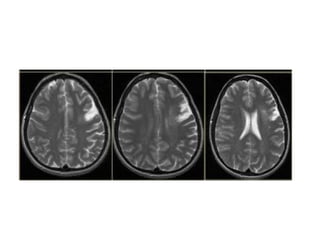

• On T2WI and FLAIR infarction is seen as

high SI.

These sequences detect 80% of

infarctions before 24 hours.

They may be negative up to 2-4 hours

post-ictus!

• High signal on conventional MR-

sequences is comparable to hypodensity

on CT.

It is the result of irreversible injury with cell

death.

So hyperintensity means BAD news: dead

brain.